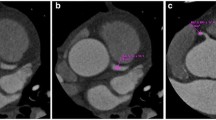

All evaluable coronary artery segments were analyzed using a four-point scale based on the modified American Heart Association 13-segment coronary artery tree [13, 14]; a score of 1 (nondiagnostic) signified impaired image quality with excessive image noise, 2 (adequate) indicated evident limitations in vessel wall definition and in contrast resolution with severe image noise, 3 (good) represented minimal limitations in vessel wall definition and in contrast resolution with moderate image noise, and 4 (excellent) denoted excellent attenuation in the vessel lumen and clear vessel wall definition with barely perceived image noise (Fig. 1).

Table 4 exhibits the objective and subjective image quality assessment results of the two groups. Although there was a tendency toward higher image noise and vessel attenuation in the study group than in the control group, the differences were statistically insignificant for both image noise (P = 0.111) and vessel attenuation (P = 0.430), as seen in Figs. 2 and 3. Consequently, there were no significant differences in SNR or CNR between the two groups.

CT scans obtained in a 57-year-old woman with a BMI of 24.1 (BMI-adapted group) using window width and level of 1,500 HU and 400 HU, respectively. a Thin-section transverse axial image, b curved multiplanar reformatted image of left anterior descending artery and c three-dimensional volume rendered image. Heart rate was 57 beats per minute. Images were scanned in the axial mode (120 kV and 400 mA) and reconstructed with AIDR 3D. The effective radiation dose was 4.0 mSv. The mean image quality score was 4, the image noise was 5.9 HU, and the left main density was 497 HU. The SNR and CNR were 77.4 and 84.2, respectively

CT scans obtained in a 60-year-old woman with a BMI of 24.1 (AEC-applied group) using a window width and level of 1,500 and 400 HU, respectively. a Thin-section transverse axial image, b curved multiplanar reformatted image of left anterior descending artery and c three-dimensional volume rendered image. Heart rate was 63 beats per minute. Images were scanned in the axial mode (80 kV and 580 mA) and reconstructed with AIDR 3D. The effective radiation dose was 1.1 mSv. The mean image quality score was 4, the image noise was 10.3 HU, and the left main density was 758 HU. The SNR and CNR were 73.6 and 84.3, respectively

The mean values of the total subjective image quality scores showed no significant differences between the two groups (P = 0.960). Furthermore, the mean scores for each segmental class did not significantly differ between the two groups (proximal, 3.57 ± 0.59 vs. 3.64 ± 0.58 for the study group vs. the control group, P = 0.668; mid, 3.47 ± 0.55 vs. 3.59 ± 0.57, P = 0.989; distal, 3.36 ± 0.56 vs. 3.52 ± 0.59, P = 0.593).